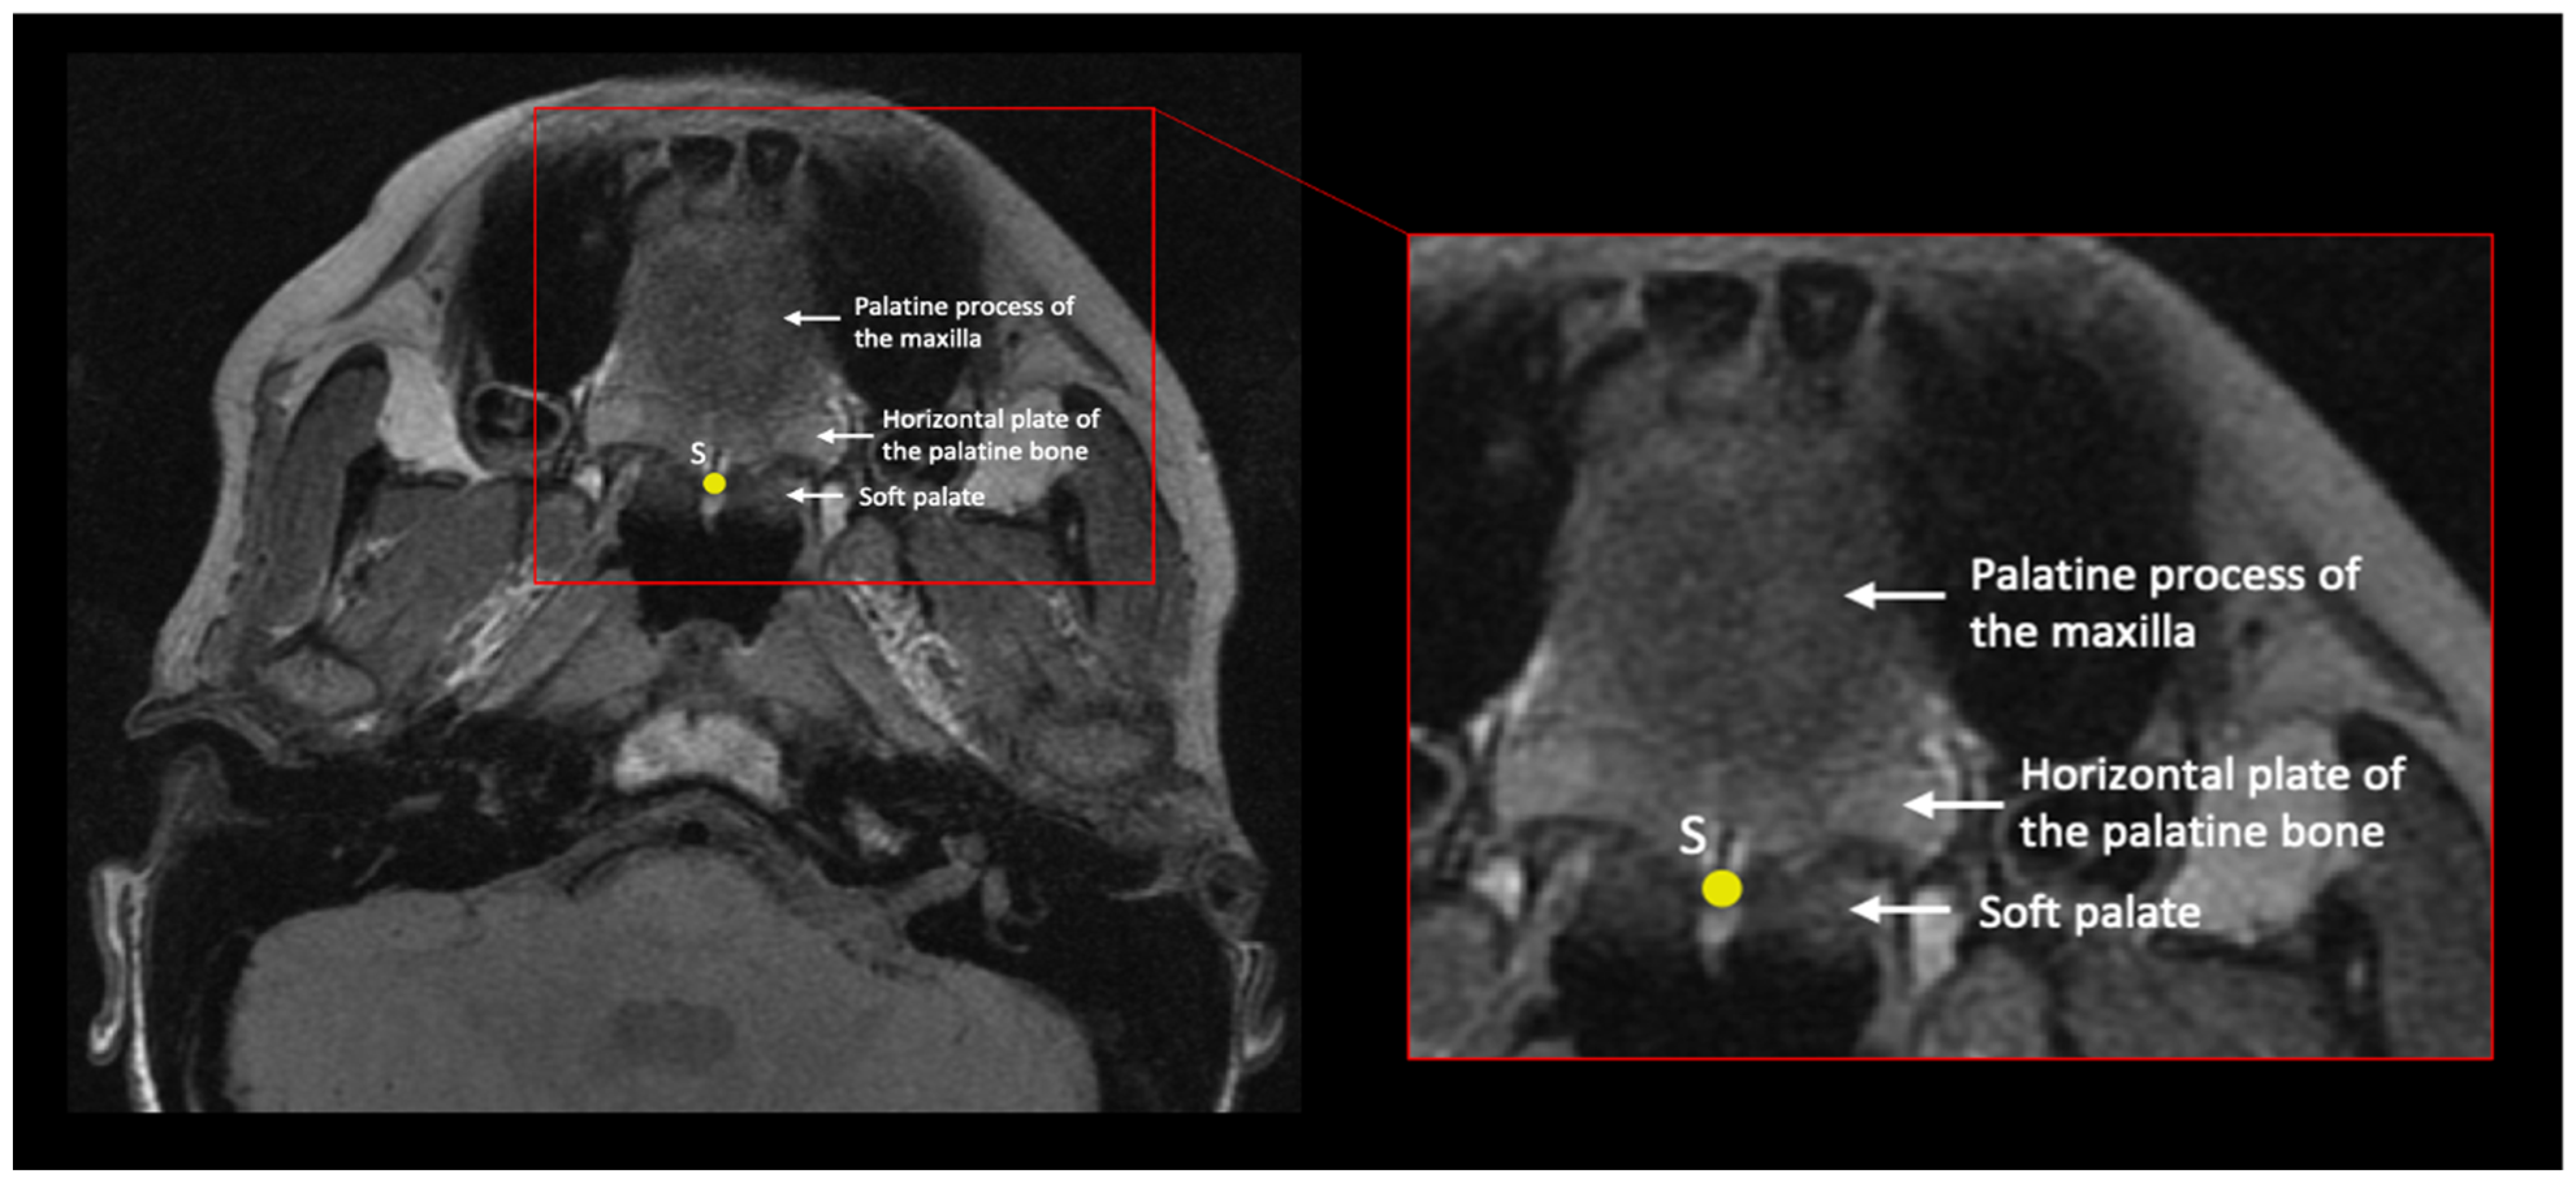

| Staphylion | S | Midline | Posterior maxillary spine | In the oblique axial plane, identify the slice that contains the maxillary palatine process and palatine bones; these form the hard palate. Place the landmark on the most posteromedial point of the palatine palate. | Figure 4 and Figure 5 |